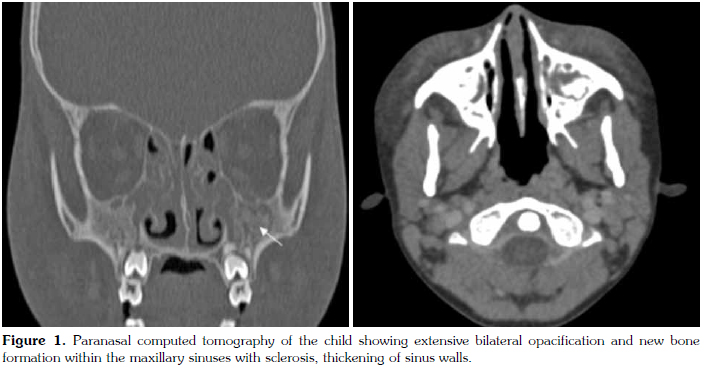

The medical history with CT findings gave a suspicion of underlying WG. Further evaluation revealed normal chest X-ray findings and complement 3 (C3) and 4 (C4) values of 154 mg/dl (79-152) and 34 mg/dl (16-38), respectively. The anti-nuclear antibody (ANA) titer was 1/80, anti-double stranded DNA (anti-dsDNA) was negative, and the myeloperoxidase antineutrophil cytoplasmic antibodies (MPO-ANCAs) was less than 2.0 U/ml (<20). Cytoplasmic-staining antineutrophil cytoplasmic antibodies (c-ANCAs) and proteinase-3 (PR3), was above 200 U/ml (<20). Thoracic CT and renal ultrasonography produced normal results. Definite diagnosis was made by punch biopsy of the maxillary sinus wall. Examination of the biopsy material revealed chronic granulomatous inflammation with numerous multinuclear giant cells, foci of microabscesses, and vasculitis consistent with WG (Figure 2). Antibiotic treatment was discontinued, while cyclophosphamide and prednisolone treatment was started.